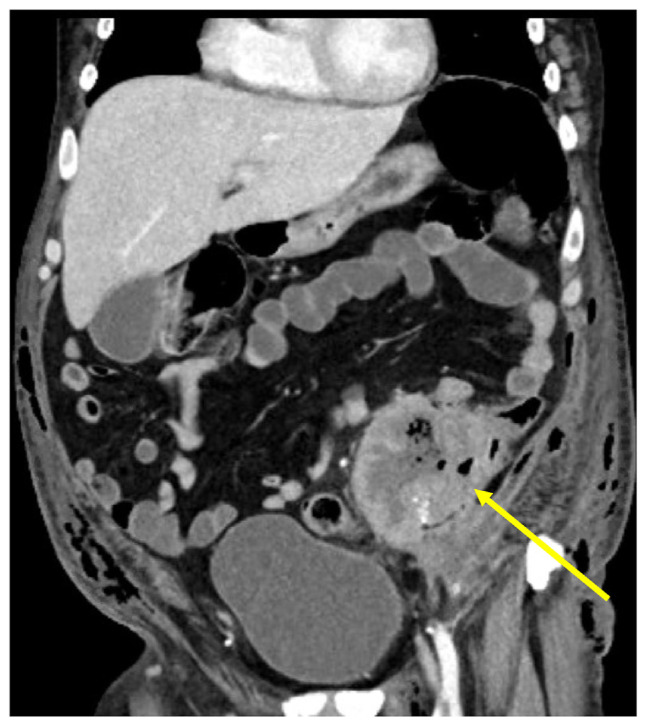

Necrotizing Fasciitis (NF) is a severe, potentially fatal soft tissue infection leading to death of muscles, fascia, and surrounding tissue. Perforated colon cancer (CC) is an exceedingly uncommon cause of NF. Here, we present a case of NF secondary to perforated colon cancer. This case emphasizes the significance of prompt identification, aggressive surgical excision of affected tissue, and consideration of rare, yet potentially fatal underlying etiologies in the management of NF as well as underscores the importance of CC screening to prevent devastating complications and mortality.